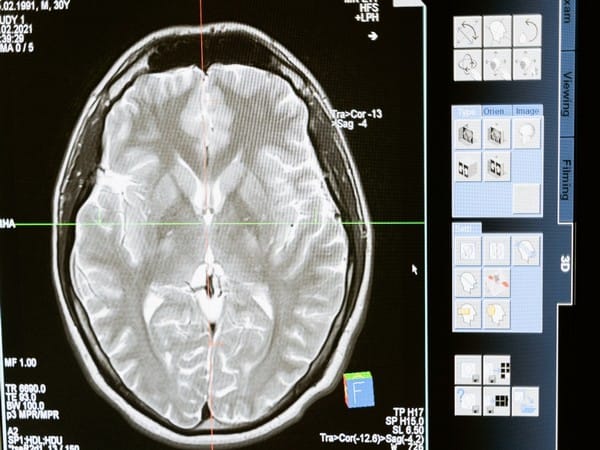

Previously, human brain temperature studies have relied upon data capture from brain-injured patients in intensive care, where direct brain monitoring is often needed. More recently, a brain scanning technique, called magnetic resonance spectroscopy (MRS), has enabled researchers to measure brain temperature non-invasively in healthy people. Until now, however, MRS had not been used to explore how brain temperature varies throughout the day, or to consider how an individual’s ‘body clock’ influences this.

The new study, led by researchers at the Medical Research Council (MRC) Laboratory for Molecular Biology, in Cambridge, UK, has produced the first 4D map of healthy human brain temperature. This map overturns several previous assumptions and shows the remarkable extent to which brain temperature varies by brain region, age, sex, and time of day. Importantly, these findings also challenge a widely held belief that human brain and body temperature are the same.